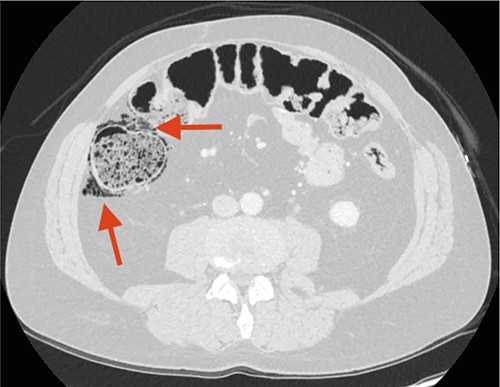

Two days later, the patient returned with intensified pain in the left flank, and a CT scan showed a calculi in the left ureter and progression in the free air located along the ascending colon (Fig. 2). The patient had no abdominal physical signs indicative of peritonitis, no fever and normal blood test.

CT scan performed 2 days after the first admission to the Emergency Department (ED). The arrow points at remaining FIA along the ascending colon/right flexure.